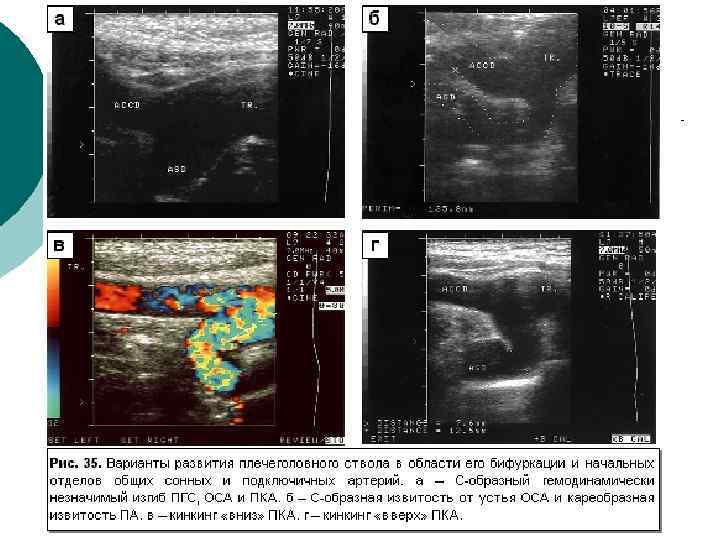

Диагностическая информативность ¡ ¡ ¡ Размеры артерий и вен; Скорости и характер движения крови; Толщина комплекса интима-медия (в норме – до 0, 8 мм в ОСА), наличие бляшек; Наличие извитостей, аневризм и стеноза артерий; Наличие тромбов, перфорантных вен при варикозной болезни, регургитации на клапанах Аномалии развития артерио-венозного русла